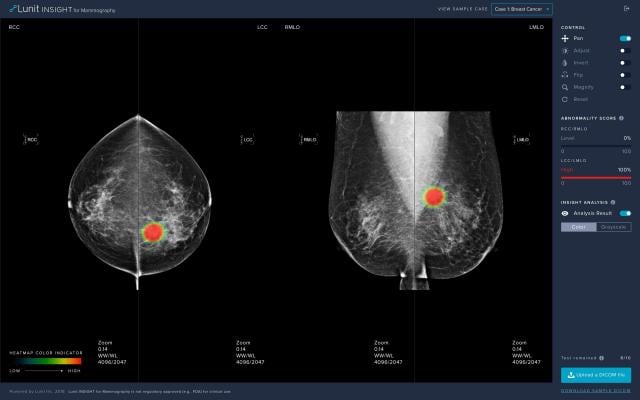

The certified software, Lunit INSIGHT MMG, publicly introduced during the 2018 Radiological Society of North America (RSNA) annual meeting, analyzes mammography images with 97% accuracy, providing the location of lesions suspicious for breast cancer, and an abnormality score that reflects the probability of the existence of detected lesions.

The study showed a significant improvement in the performance of radiologists, before and after using AI. According to the study, the AI alone showed 88.8% sensitivity in breast cancer detection, whereas radiologists alone showed 75.3%. When radiologists were aided by AI, the accuracy increased by 9.5% to 84.8%.

One of the major findings also showed that AI, in comparison to the radiologists, displayed better sensitivity in detecting cancer with mass (90% vs 78%) and distortion or asymmetry (90% vs 50%). The AI was better in the detection of T1 cancers, which is categorized as early-stage invasive cancer. AI detected 91% of T1 cancers and 87% of node-negative cancers, whereas the radiologist reader group detected 74% for both. The findings revealed that the diagnostic performance of AI was less affected by breast density, whereas radiologists’ performance was prone to density.